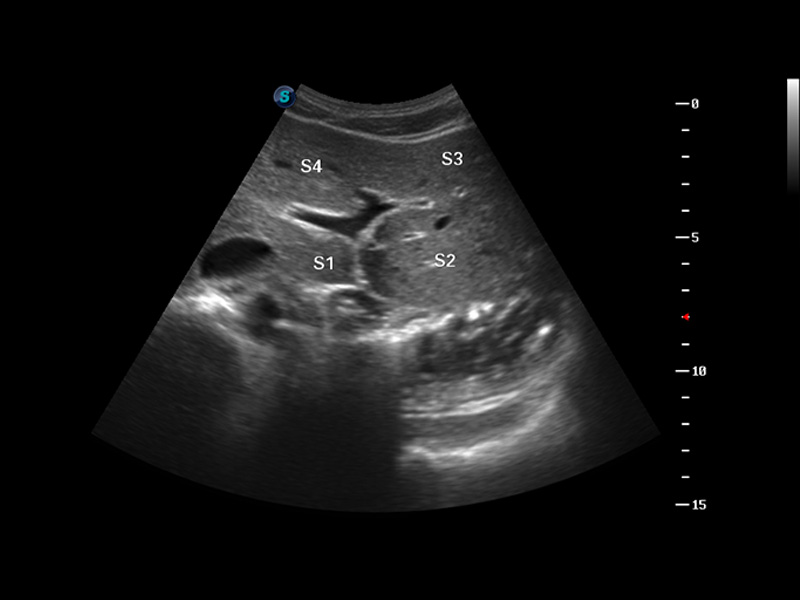

S8 EXP便携式彩色多普勒超声诊断仪是乐玩lewin国际研发的高端全身应用型便携彩超。高通道的VIS平台融合可视化(Visual)、智能化(Intelligent)和人性化(Smart)的特点,配以乐玩lewin国际自主研发生产的探头大家族,使您能够快速、准确的获得病人信息,提高工作效率的同时减轻疲劳。

3D/4D成像